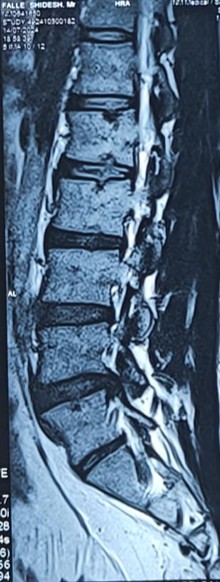

Infections can affect the bones or discs of the spine. They can cause fever, pain, and may need urgent care to prevent serious problems.